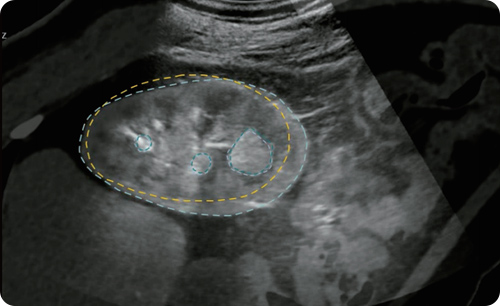

Real-time guide and CT-Ultrasound fusion in pixel level to achieve precise access.

3D reconstruction to show the organs, lesions and instrument in realtime.